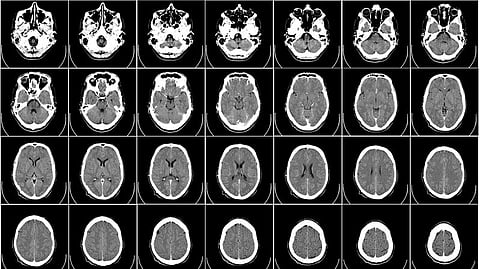

The brain is a complex organ, and no one imaging mode can catch everything that’s going on inside it. Over the years, multiple “brain maps” have emerged, each focusing on different brain processes, from metabolism to cognitive function. While these maps are important, using them in isolation limits the discoveries researchers can make from them.

Now a team from The Neuro has brought together more than forty existing brain maps in one place. The database, called neuromaps, will help scientists find correlations between patterns across different brain regions, spatial scales, modalities and brain functions. It provides a standardized space to view each map in comparison to each other, and assesses the statistical significance of these comparisons, to help researchers distinguish a meaningful correlation from a random pattern. The neuromaps database also helps standardize the code across maps, to improve reproducibility of results.